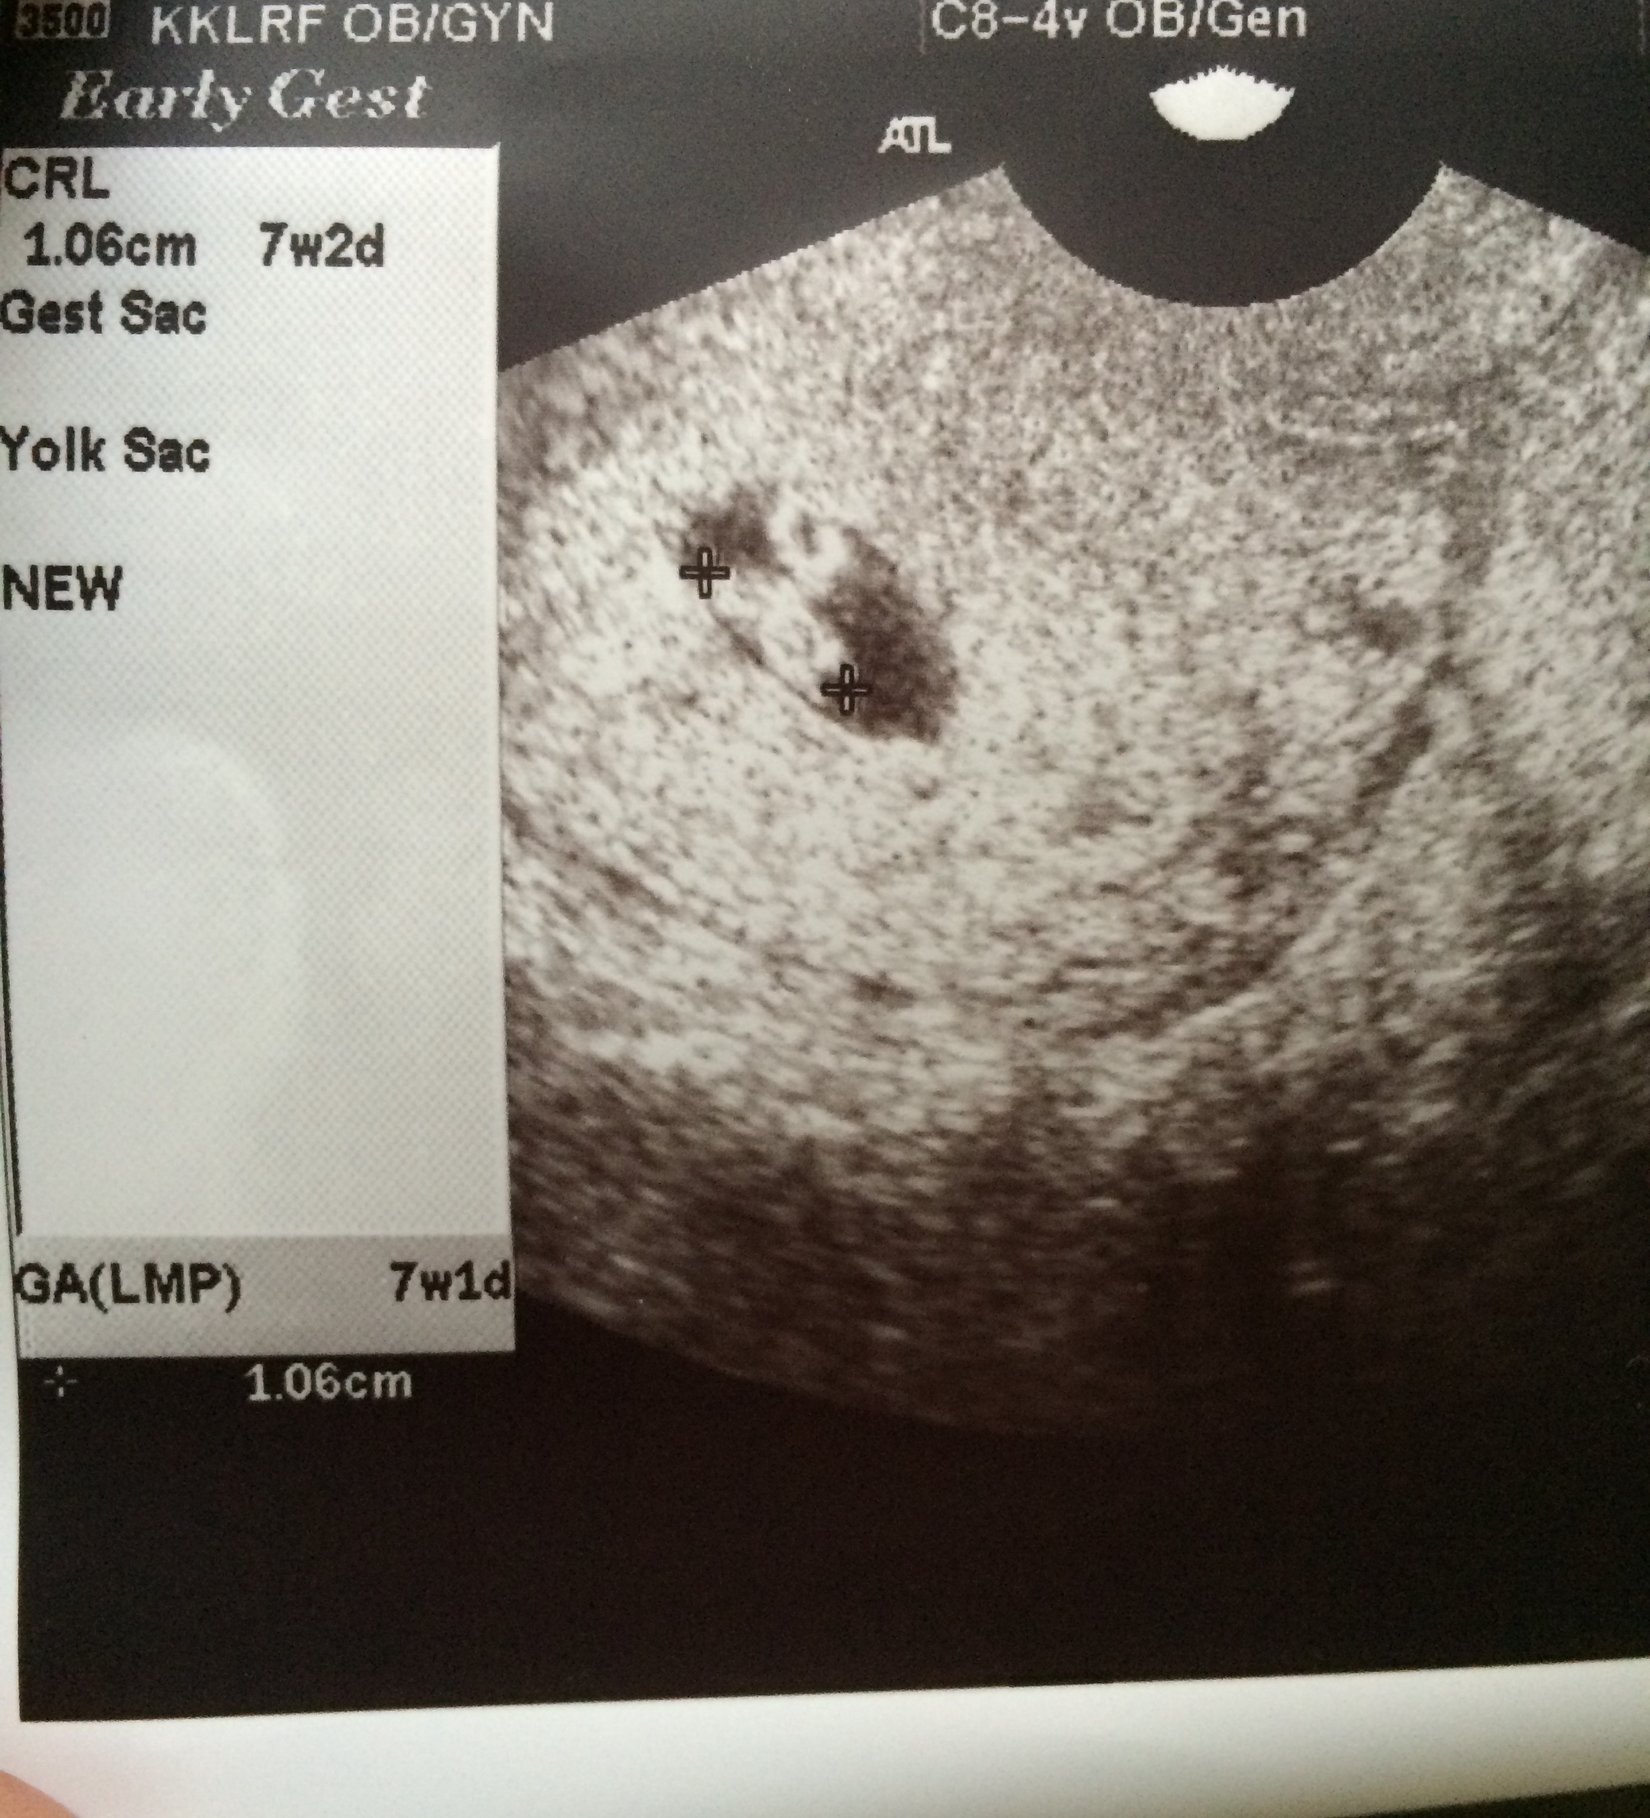

I still have the fear in the back of my mind (this ultrasound will be at 7w1d, and our first baby stopped growing at 7w1d), but I am still excited that things are looking good so far.

I got my test results today, my HCG level was 29,983. The doctor called me today to let me know that these results looked good and that my levels were progressing enough for her. Now I have my first ultrasound in 1 week! I'm so excited!